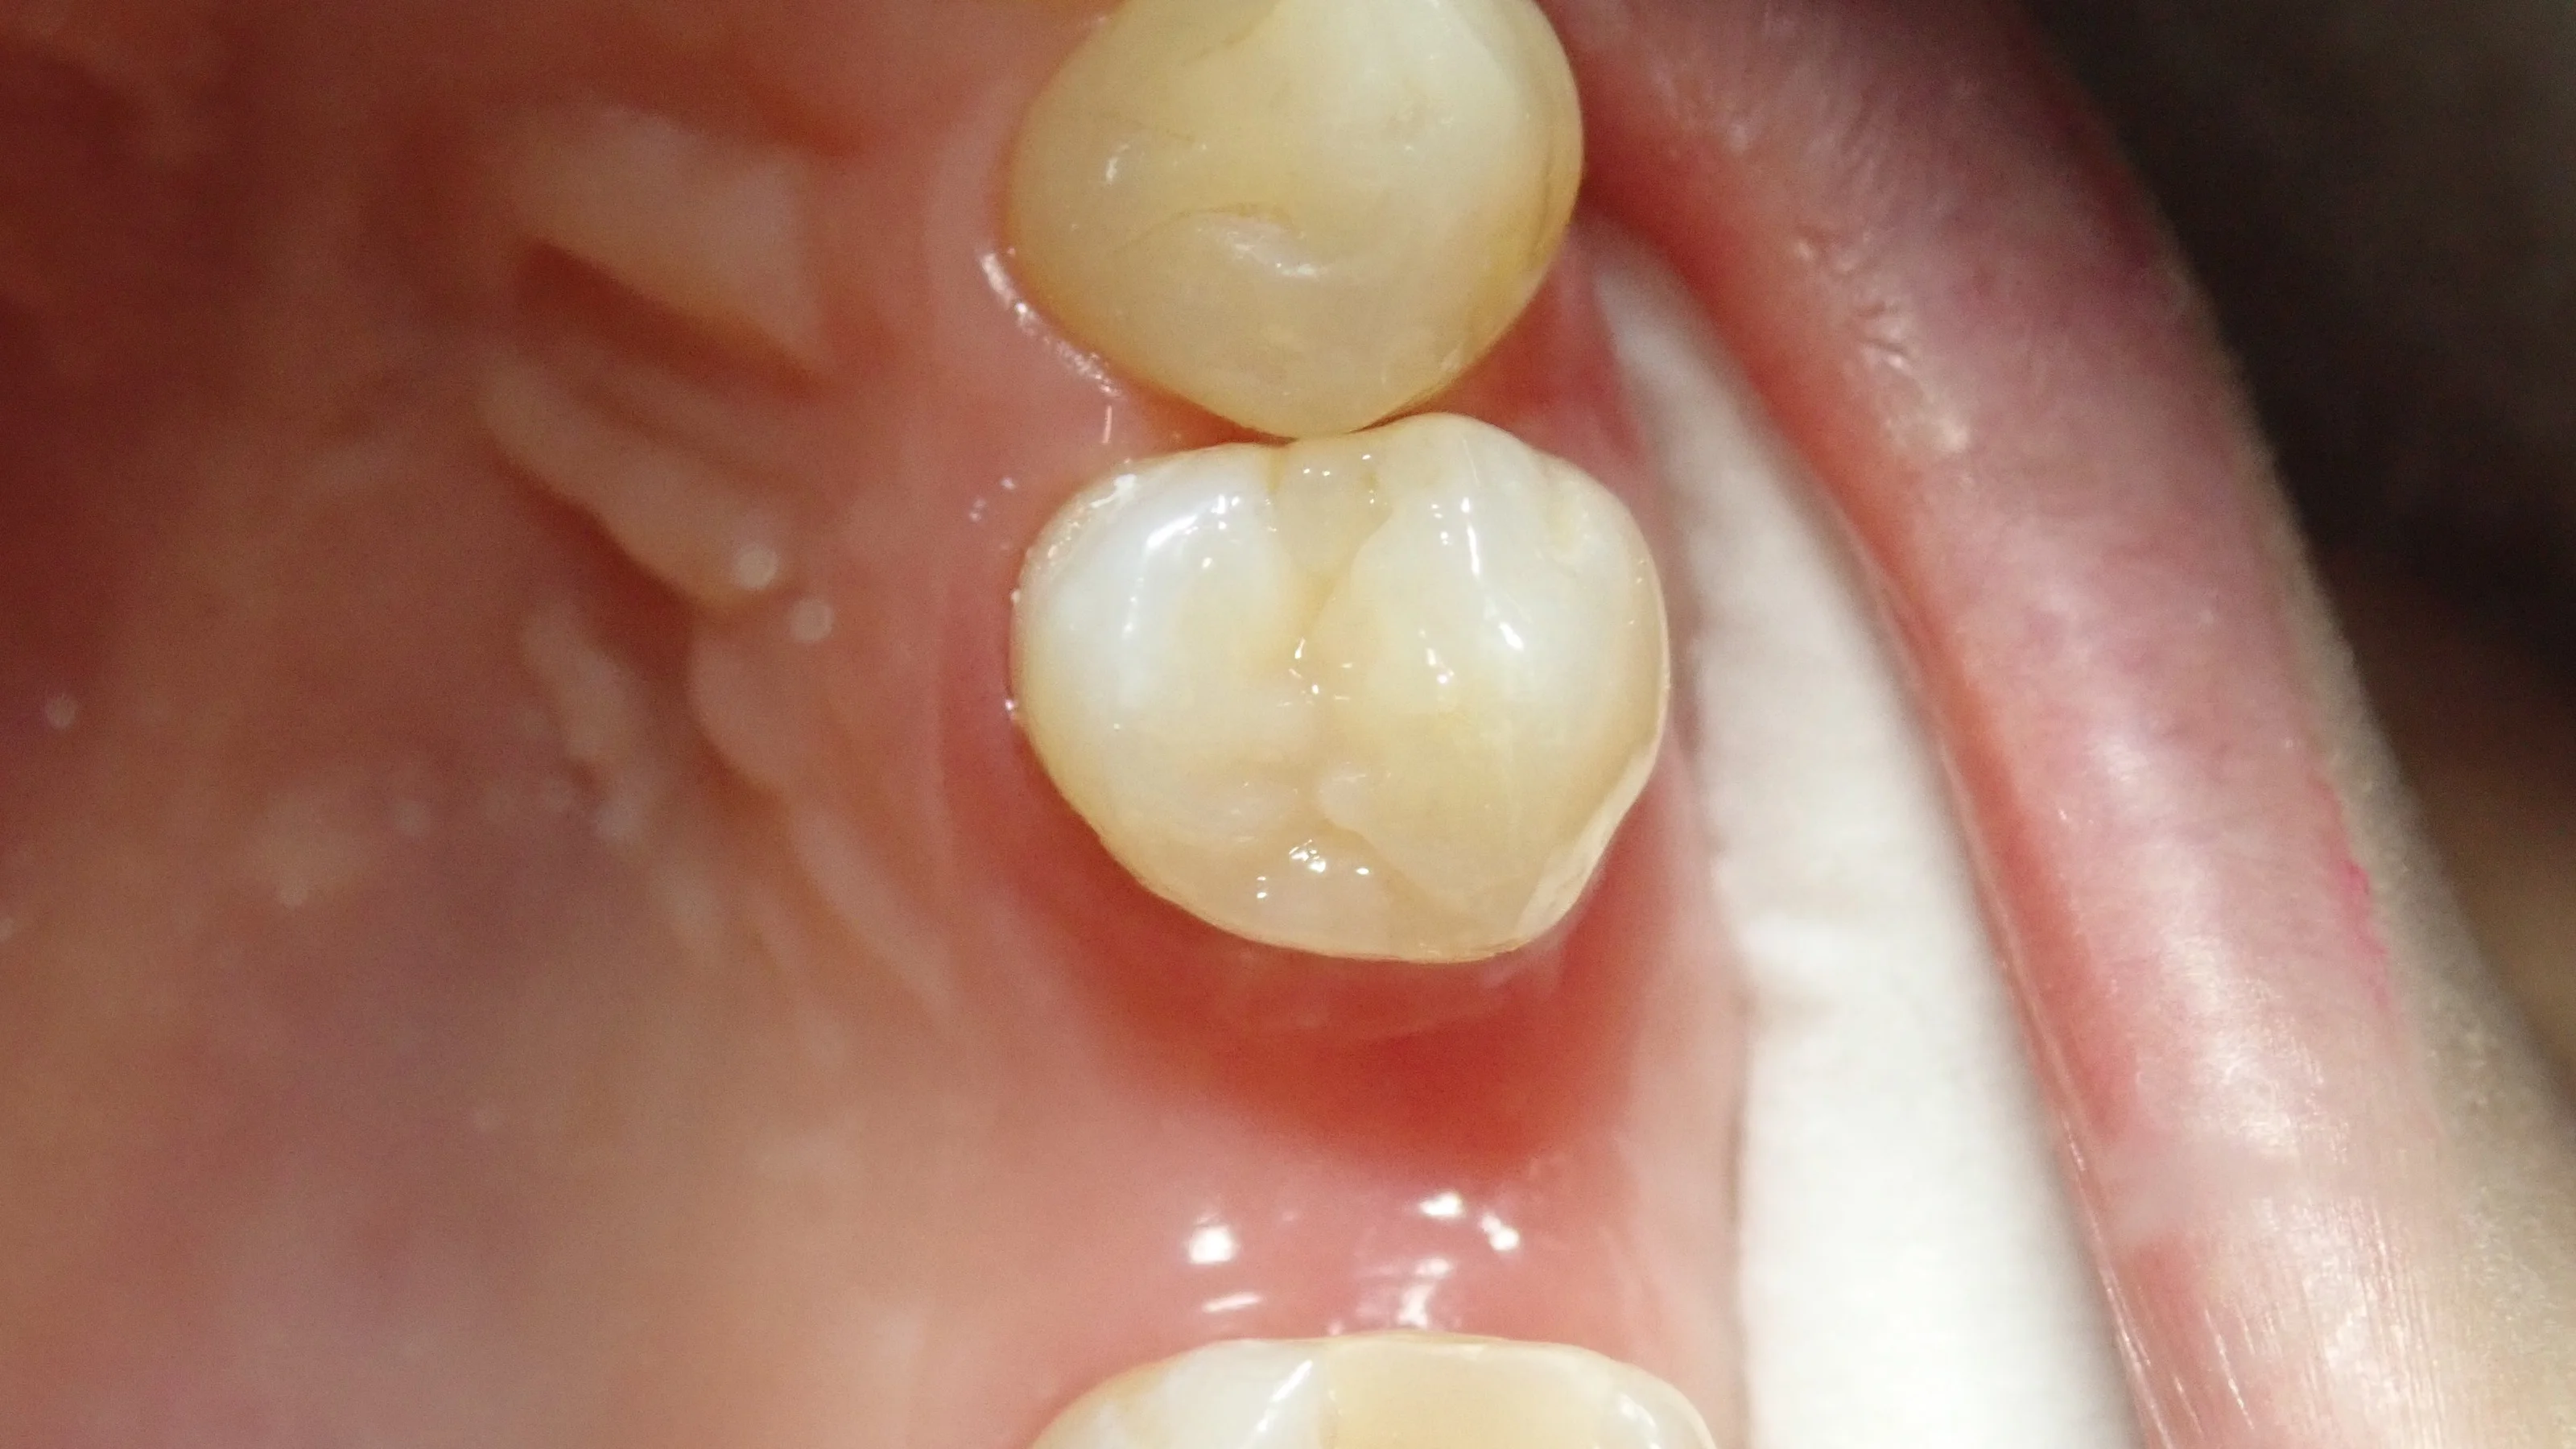

で、中断していたダイレクトボンディングを完了したのがこちら。

こちらの患者さんはステイニングを希望されなかったので、一切着色を使用せずに行いました。

ステイニングを行っていない為、立体感は乏しいですが、パット見た時の違和感はないようにできたと思います。